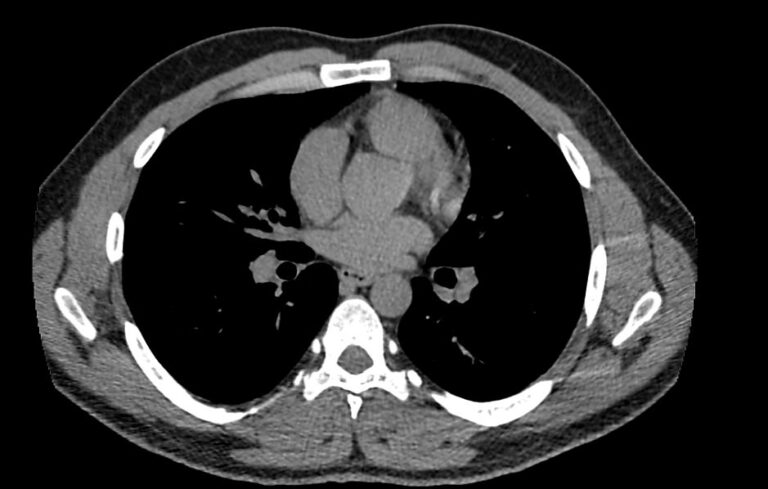

Одним из наиболее информативных методов исследования органов средостения является компьютерная томография. В основе метода лежит использование проникающего действия ионизирующего излучения для получения подробных снимков строения внутренних органов.

Инновационные технологии, которыми оснащены компьютерные томографы, послойно сканируют анатомическую область с шагом от 0,5 мм. В результате получаются снимки тонких срезов исследуемой зоны в мельчайших подробностях. С помощью цифровых приложений на основании полученных данных можно реконструировать трехмерные модели внутренних органов, что позволяет оценить структуру зоны исследования и близлежащих тканей.

- Что показывает КТ органов средостения?

Что показывает КТ органов средостения?

- наличие онкологии и метастазов;

- туберкулез и другие инфекции;

- патологии диафрагмы и бронхов;

- последствия травм;

- состояние лимфоузлов;

- индивидуальные анатомические особенности;

- патологии вилочковой железы;

- новообразования из нервной ткани;

- опухоли в жировой соединительной ткани;

- патологии мышечной ткани и сосудов;

- кисты;

- эмфизему средостения;

- абсцесс, эмпиему средостения;

- аневризму аорты

- воспалительные процессы;

- болезни сосудов и тромбоэмболию.